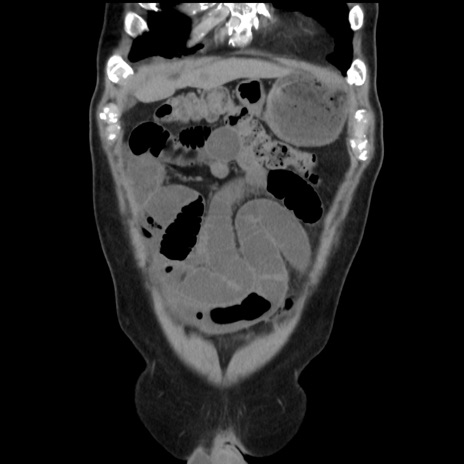

症例16(冠状断像)

【症例】 70歳代男性

【主訴】 腹痛、嘔吐

【現病歴】 約1ヶ月前より間欠的に腹痛と嘔吐あり、当院消化器内科を受診したところCTで多発する肝臓のLDAを指摘され、精査中であった。以降は消化器症状は安定していたが、2日前より嘔気と腹痛があり、同日より排便・排ガスが消失した。改善認めず、 本日、救急外来を受診した。

【既往歴】 大腸ポリープ切除後。

【身体所見】意識清明・会話良好、BT 36.3℃、BP 127/80mmHg、 P 80bpm、腹部:膨満あり、平坦・軟、上腹部正中および下腹部正中に圧痛あり、反跳痛なし、筋性防御なし。

【データ】WBC 7200、CRP 0.77